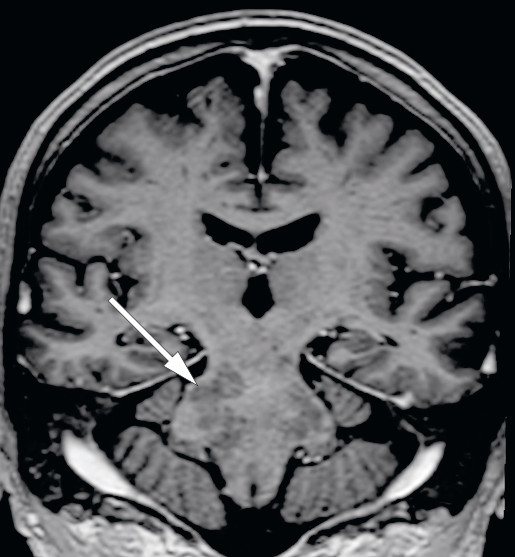

MR av hodet tatt en måned etter utskrivelse viste multiple lesjoner med høyt signal på T2-vektet serie og FLAIR (fluid-attenuated inversion recovery) i den forlengede marg, hjernebroen, midtre lillehjernestilk, venstre lillehjernehemisfære, midthjernen på venstre side og i basalganglieregionen på venstre side (figur 1). Det var også en liten lesjon i øvre del av ryggmargen i nivå C1 på venstre side samt subkortikalt parietalt på venstre side. Etter injeksjon av kontrastmiddel var det varierende grad av punktformet og stripeformet kontrastladning, som stedvis var konfluerende (figur 2). MR-angiografi av hjernearterier viste en liten stenose i høyre bakre hjernearterie, som ble oppfattet som aterosklerotisk betinget. Det var ellers normale arterier. En var på dette tidspunktet usikker på hva forandringene representerte, og pasienten ble innlagt på nevrologisk avdeling samme dag for utredning.

Syndromet som kalles CLIPPERS – chronic lymphocytic inflammation with pontine perivascular enhancement responsive to steroids – er en relativt nylig definert inflammasjonstilstand i sentralnervesystemet som hovedsakelig rammer hjernestammen, særlig hjernebroen. Tilstanden ble først beskrevet i 2010 (1) som en form for hjernestammeencefalitt lokalisert i hjernebroen, kjennetegnet av predominant T-celle-patologi og av at den responderer på immunsuppresjon med glukokortikoider. Symptomene er hovedsakelig knyttet til involvering av hjernestammen, spesielt gangataksi og dobbeltsyn. Andre symptomer inkluderer dysartri, endret sensibilitet og parestesier i ansiktet, svimmelhet, nystagmus, spastiske parapareser og pseudobulbær affekt. MR hos vår pasient viste karakteristisk mønster i form av perivaskulær kontrastladning i hjernebroen og andre deler av bakhjernen (1).

MR-funn er karakteristiske og spiller en avgjørende rolle i diagnostiseringen (3). Karakteristiske trekk er homogene, kontrastladende lesjoner større enn 3 mm i diameter, uten masseeffekt predominerende i hjernebroen og lillehjernen, med tydelig reduksjon av kontrastladning etter steroidbehandling. Lesjoner kan strekke seg til nærliggende sentralnervesystemstrukturer, kaudalt til den forlengede marg og ryggmargen, samt til supratentoriale regioner som talamus, capsula interna, basalgangliene, hjernebjelken og hvit substans (1, 3, 8).